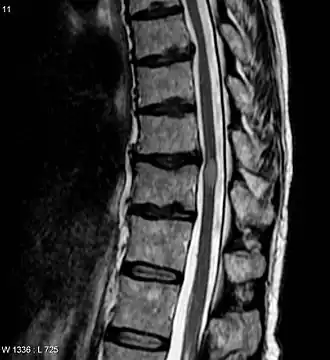

Le bilan est appuyé par la résonance magnétique nucléaire (y a-t-il une lésion unique ou multiple au niveau de la moelle ?) rehaussée par l'administration intraveineuse de gadolinium. Une ponction lombaire recherche une pléiocytose, une bande oligoclonale au niveau des IgG[8].